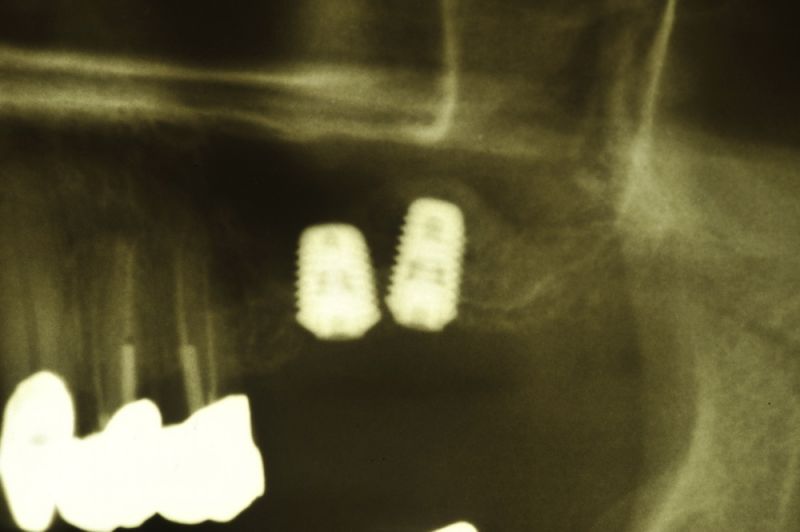

Am heutigen Tag sind in regio 26 und 27 zwei Implantate mit einem externen Sinuslift versorgt worden. Die Besonderheit des Eingriffs liegt darin, dass im Oberkieferseitenzahnbereich, bei einer noch vorhandenen Restknochenhöhe von wenigen Millimetern, zwei Implantate gesetzt und gleichzeitig eine Aufdoppelung des vorhandenen Restknochenangebots, durch die Schaffung eines Raumes zwischen knöcherner Abgrenzung der Kieferhöhle und der in die Kieferhöhle hinein verdrängten Kieferhöhlenmembran geschaffen werden konnte.

Genau das kann man dann auf dem Röntgenbild erkennen. So bildet sich innerhalb der Kieferhöhle, aber begrenzt durch die Kieferhöhlenmembran, neuer Knochen, der dann nachfolgend dem Implantat den knöchernen Halt gibt, den es unter späterer Belastung durch Kaudruck benötigt.